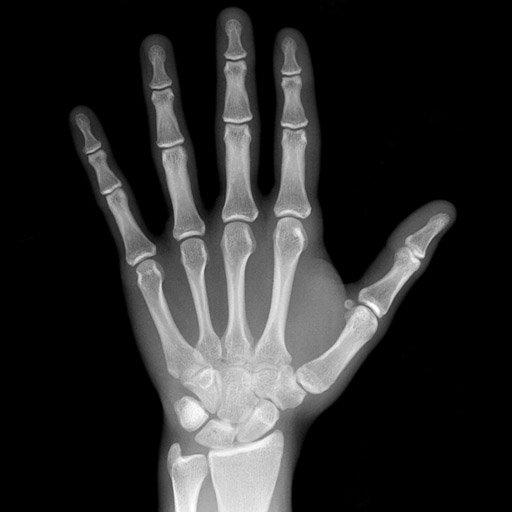

Image Test Data – The Image Retrieval in Medical Applications (IRMA) database222http://irma-project.org/ is a collection of more than 14,000 x-ray images (radiographs) randomly collected from daily routine work at the Department of Diagnostic Radiology of the RWTH Aachen University333http://www.rad.rwth-aachen.de/ [8, 17]. All images are classified into 193 categories (classes) and annotated with the IRMA code which relies on class-subclass relations to avoid ambiguities in textual classification [10, 9]. The IRMA code consists of four mono-hierarchical axes with three to four digits each: the technical code T (imaging modality), the directional code D (body orientations), the anatomical code A (the body region), and the biological code B (the biological system examined). The complete IRMA code subsequently exhibits a string of 13 characters, each in {0,,9;a,,z}09𝑎𝑧\{0,\dots,9;a,\dots,z\}: TTTT-DDD-AAA-BBB. More information on the IRMA database and code can be found in [8, 9]. IRMA dataset offers 12,677 images for training and 1,733 images for testing. Figure 4 shows some sample images from the dataset along with their IRMA code in the format TTTT-DDD-AAA-BBB. IRMA x-rays images are a challenging benchmarking case mainly due to the imbalanced class distribution.

Refer to caption

(a) 1121-127-700-500

(b) 1121-120-942-700

(c) 1121-120-200-700

(d) 1121-120-918-700

Fig. 4: Sample images from IRMA Dataset with their IRMA codes TTTT-DDD-AAA-BBB.